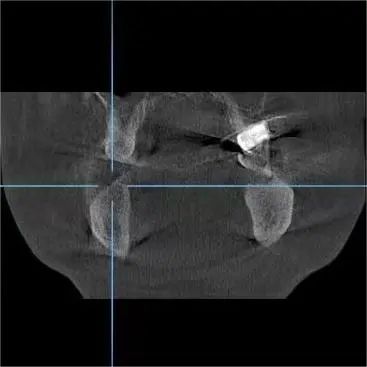

种植专家、口腔科杨彦春主任检查发现其口腔卫生环境较差,缺失的又是需要咀嚼的后牙,建议行种植修复手术。

术中,王先生血压、血氧稳定,仅用半小时,杨彦春主任顺利为其开展两颗种植牙手术。